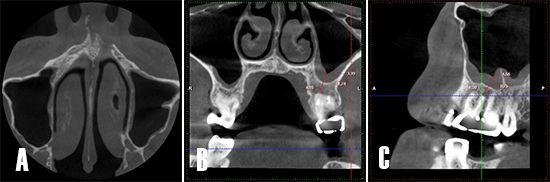

Control tomográfico a los 12 meses. A) Corte en el plano axial: se observa la cavidad sinusal sin opacificación. B) Corte coronal: se observa la cavidad sinusal limpia, la zona apical se observa más radiodensa, lo que sugiere la formación de hueso nuevo. C) Corte sagital: se aprecia cómo el engrosamiento de la membrana se asocia a la presencia del septo óseo del seno maxilar.

Figura 8. Control tomográfico a los 12 meses. A) Corte en el plano axial: se observa la cavidad sinusal sin opacificación. B) Corte coronal: se observa la cavidad sinusal limpia, la zona apical se observa más radiodensa, lo que sugiere la formación de hueso nuevo. C) Corte sagital: se aprecia cómo el engrosamiento de la membrana se asocia a la presencia del septo óseo del seno maxilar.